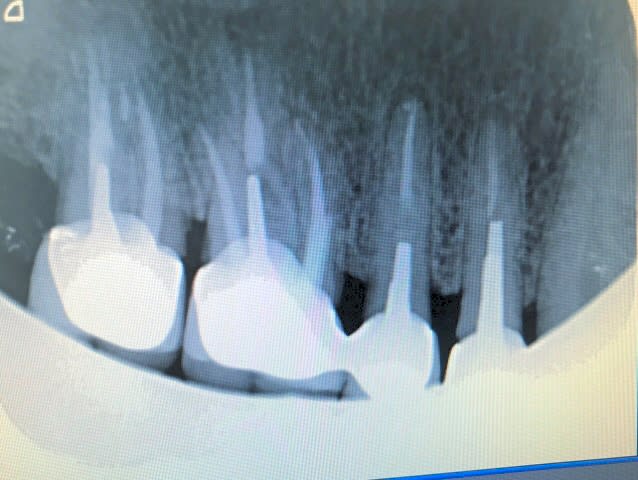

Mais là c'est pas très evident sur la radio prise par un confrère

Vous avez meilleure vue vous.

L'image est helas peu exploitable, 92 k....

La reprendre en haute définition. J'ai essayé d'affiner contraste/saturation , mais sur du 92k, c'est limite!

Sinon, on voit vaguement une solution de continuité oblique a la limite du pivot (felure, fracture), une resorption assez importante un peu plus haut, et une petite image apicale.

L'insertion douloureuse du pivot me fait penser a la fracture/felure....

Il y a une fracture de la racine la plus courte, en regard de l'extrémité du tenon.

inlay core à clavette sur 14 c'est quasiment sur q'uil y a une fracture radiculaire

15 me parait devoir etre plus en cause que 14

je vois un epaississement significatif sur 15 contrairement a 14